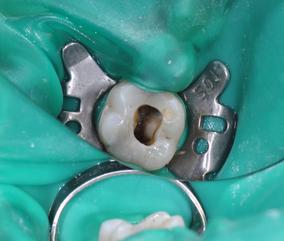

ENDODONTICS

Following an Endodontic referral, patients are seen for a detalied consultation with digital radiographs. The restorability of the tooth and the endodontic outcome are discussed along with treatment options.​​

The Endodontic set up is State of the Art, including a microscope, digital radiographs, rotary NiTi instrumentation, thermoplastic obturation, electronic apex locators and Ultrasonic equipment.